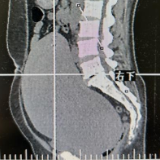

宫颈肌瘤因位置特殊,手术视野暴露困难,极易误伤紧邻的输尿管、直肠等关键器官,并且血供网络异常丰富,术中极易发生难以控制的大出血,止血挑战巨大。面对这一挑战,科主任赵璟迅速集结了一支经验丰富的“拆弹专家”团队,术前通过影像导航锁定肌瘤位置,精准定位“雷区”,联合麻醉、泌尿外科专家多学科协作,其中一位患者术中临时放置输尿管支架,制定个性化“拆弹路线”,术中毫米级精细操作在血供丰富的瘤体周围谨慎分离, 成功为宫颈肌瘤患者实施子宫切除手术,保障患者手术安全,术后病理均提示良性平滑肌瘤,压在患者及其家属心头巨石终于落地。